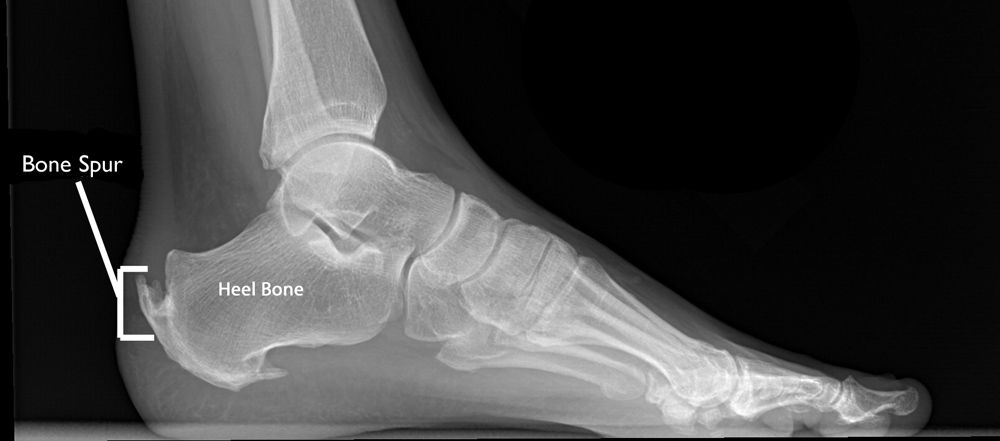

Calcaneal Spur And Calcification Arrow Were Observed In The Download Scientific Diagram